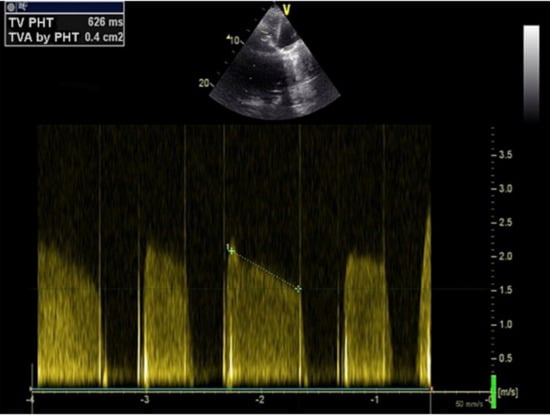

The 7F sheath and the pigtail were removed, and a 16F Edwards eSheath Introducer was inserted. The Edwards Delivery System with the Sapien 3 29 mm valve (Edwards Lifesciences, Irvine, CA, USA) was passed through the introducer. Under fluoroscopic (C-arm perpendicular to the bioprosthetic valve annulus) and TEE guidance, the system was advanced to the annulus of the degenerated bioprosthetic valve that served for accurate alignment and positioning of the transcatheter valve. Fine adjustment was carried with the balloon catheter (pulling and rotating to optimal centering of the valve). Prior to valve deployment, rapid pacing was initiated using the Confida guide wire as a cathode while the anode was placed in the subcutaneous tissue of the right inguinal region. The Sapien 3 valve was then deployed by expanding the balloon to the nominal pressure value with excellent results (Figure 4).

The delivery system, the introducer sheath and the guide wire were removed after confirming the position and the competence of the TTVIV by TEE (Figure 5). After extracting all materials, the two purse strings were ligatured followed by meticulous hemostasis. The right lung was reinflated using the Valsalva maneuver and a drainage catheter was inserted in the right costodiaphragmatic recess before closing the thoracotomy site. Postoperative evolution was uneventful, and the patient was discharged after two weeks with NYHA class II heart failure compared to IV at admission.

Figure 4. Fluoroscopic image showing the normofunctional Edwards Sapien 3 valve-in-valve after deployment.